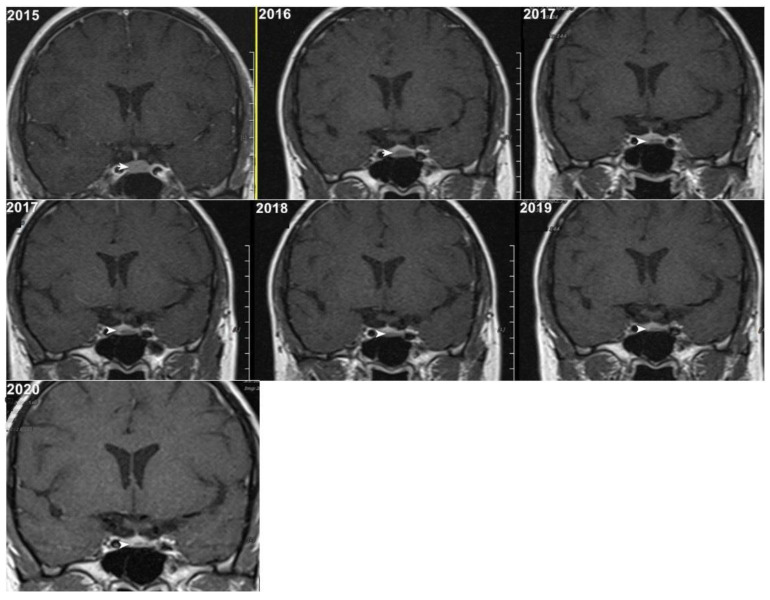

简介和目的:动态对比增强磁共振成像(DCE-MRI)已被用作诊断和跟踪垂体微腺瘤的金标准。然而,钆基造影剂(gbca)的使用存在长期滞留组织和不良反应的潜在风险。本研究旨在评估非对比MRI (T1W和T2W序列)在垂体微腺瘤随访成像中的敏感性,并试图与DCE-MRI进行比较,评估肿瘤随时间的稳定性。材料和方法:我们回顾性分析了2020年至2024年间300例垂体MRI扫描。纳入确诊的微腺瘤(≤10 mm)患者。非对比(T1W/T2W)和DCE-MRI序列由经验丰富的放射科医生对任何临床信息进行分析。评估检出率和肿瘤大小的变化。结果:79例微腺瘤T1W检出率为55.7%,T2W检出率为70.9%,DCE-MRI检出率为88.6%。随访期间未见明显肿瘤生长(平均大小4.80±2.3 mm vs. 4.81±2.4 mm, p < 0.05)。结论:虽然对早期诊断更为敏感,但非对比MRI能够显示大多数检测到的微腺瘤,并排除明显生长的病例,因此支持在稳定病例的随访影像学中省略钆。这可能转化为更低的成本和降低患者的风险,从对比相关的危害。

Introduction and objectives: Dynamic contrast-enhanced magnetic resonance imaging (DCE-MRI) has been used as a gold standard in diagnosing and following pituitary microadenomas. However, the use of gadolinium-based contrast agents (GBCAs) involves a potential risk of long-term retention in tissues and adverse reactions. This study aimed to evaluate the sensitivity of non-contrast MRI (T1W and T2W sequences) in follow-up imaging of pituitary microadenomas, attempting a comparison with DCE-MRI, assessing tumor stability over time.

Materials and methods: We retrospectively reviewed 300 pituitary MRI scans between 2020 and 2024. Included were patients with confirmed microadenomas (≤10 mm). Non-contrast (T1W/T2W) and DCE-MRI sequences were analyzed by an experienced radiologist blinded to any clinical information. Detection rates and changes in tumor size were evaluated.

Results: Detection rates for 79 microadenomas were 55.7% for T1W, 70.9% for T2W, and 88.6% for DCE-MRI. There was no significant tumor growth during the follow-up (mean size 4.80 ± 2.3 mm vs. 4.81 ± 2.4 mm, p > 0.5).

Conclusions: While still more sensitive for the primary diagnosis, the non-contrast MRI was able to visualize the majority of detected microadenomas, and significant growth was ruled out, thus supporting the case to omit gadolinium from follow-up imaging in stable cases. This may translate to lower costs and decreased patient risk from contrast-related hazards.